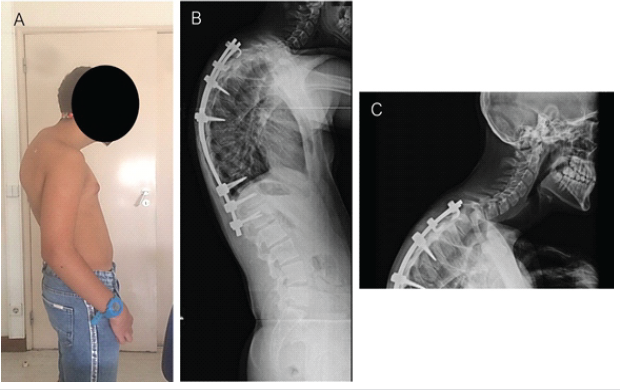

During the initial 2 months after surgery, the patient experienced improved posture and significant pain relief. However, at subsequent follow-up, he developed progressive back pain and radiographic evidence of loss of correction at the proximal junction. At 8 months postoperatively, imaging demonstrated an increased proximal junctional angle above the UIV, consistent with PJK (Fig. 3).

Figure 3: (a) Examination showing prominent upper back kyphosis at the cervicothoracic spine junction; and (b and c) 8-month post-operative spine lateral view radiographs showing a proximal junctional kyphosis.